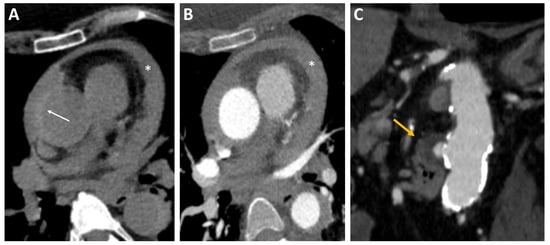

Non-contrast CT from the supraortic vessels to the aortic carrefour is crucial to diagnosing IMH. IMH is visible on unenhanced CT typically as an eccentric, hyperdense (60–70 HU), crescentic area of thickening of the aortic wall (>0.5 cm), showing no enhancement after administration of intravenous contrast that extends in a longitudinal, non-spiral fashion (Figure 3A,B). The sensitivity and specificity values of CT for IMH are close to 100% [44]. In addition to the well-known limitations of this technique, another limitation is the difficulty in differential diagnosis with aortitis. Type A IMH is at higher risk of evolving towards overt dissection and is associated with the increased incidence of hemopericardium and cardiac tamponade. Management of IMH type A is usually surgical [45].

Figure 3.

Intramural hematoma on CT using (A) non-contrast CT and (B) CT angiography: crescentic, high-attenuating regions of eccentrically thickened aortic wall on non-contrast CT (arrow). A diffuse pericardial effusion (*) was also visible in both scans. (C) Penetrating ulcer on CT: CT angiography image showing a penetrating ulcer of the descending aorta as a contrast-filled, out-pouching into the thickened aortic wall (arrow). CT, computed tomography.

Other CT findings that can be useful to predict the negative evolution of the IMH include an IMH high mean IMH thickness greater than 10–11 mm, compression of the true aortic lumen, a maximal ascending aortic diameter greater than 50 mm, or descending aorta greater than 45 mm, association with PAU, and the presence of pericardial effusion [46]. These high-risk features can help to decide the management of type B IMH if conservative or interventional using TEVAR.

CT characteristic features of PAU are an aortic out-pouching in the presence of aortic intima calcifications and severe atherosclerotic disease. The edges of the out-pouching are usually irregular or jagged [55] (Figure 3C). PAU can be distinguished with CT from ulcerated aortic plaque. The latter is a minimal disruption of the intima without the involvement of the media layer of the aorta. On CT images, ulcerated plaques appear like a crater within an atherosclerotic plaque which, in contrast to PAU, does not alter the aortic outline [56].

CT imaging can be helpful in stratifying the risk of patients with PAU to select the appropriate management. In particular, patients with PAU diameters over 13–20 mm and more profound than 10 mm and concomitant IMH are associated with a worse prognosis [57]. Choosing this technique, the risk of nephropathy and allergy induced by contrast medium and use of ionizing radiation must be considered.